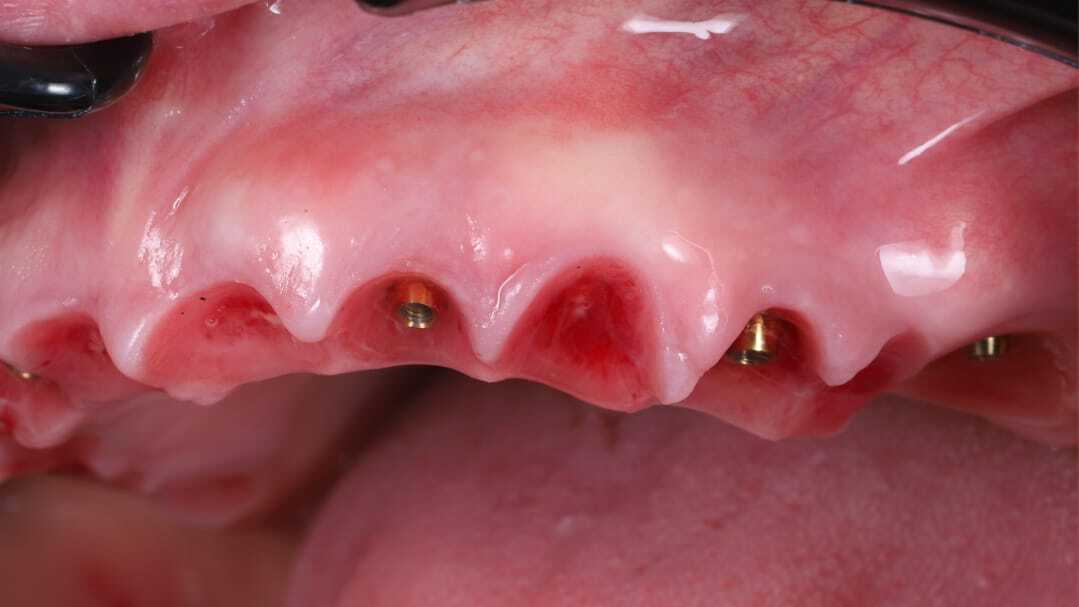

Константин Олегович Юшков

Планирование от результата. Выбор количества опор и материала постоянной конструкции. Работа с мягкими тканями на этапе провизорных.

До

После

Цифровые протоколы немедленной нагрузки с умеренной степенью атрофии